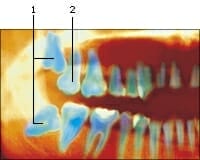

Geïmpacteerde kiezen

Klachten en verschijnselen – Pijnlijk tandvlees. ...